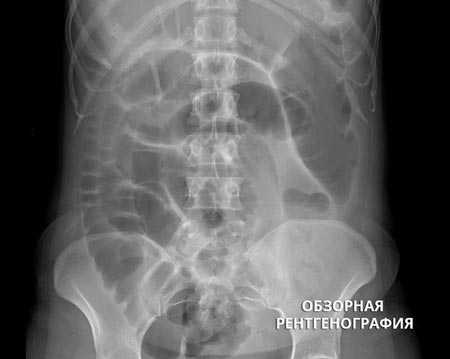

Инструментальные исследования, необходимые для определения синдрома, проведенные до госпитализации в организацию по оказанию паллиативной помощи:при острых состояниях ― простой рентгенологический снимок живота (если есть признаки кишечной непроходимости или скопление большого количества каловых масс в толстом кишечнике).

Рентгенография ОБП при кишечной непроходимости

Если у онкологического больного появились признаки кишечной непроходимости, его нужно срочно госпитализировать в стационар. Самый простой и быстрый способ диагностики кишечной непроходимости — обзорная рентгенография брюшной полости. На снимках можно увидеть раздутые газом участки кишки, скопление жидкости. Один из характерных симптомов — так называемые чаши Клойбера — скопления воздуха и жидкости, которые внешне напоминают перевернутые чаши или буквы «U». [2,12]

Наиболее простой, быстрый и доступный метод диагностики – это обзорная рентгенография органов брюшной полости. На снимках обнаруживаются характерные признаки:

- Чаша Клойбера – видны расширенные петли кишечника в виде куполов, и в них горизонтальный уровень жидкости. Эта картина напоминает перевернутую вверх дном чашу. Чаш может быть несколько, на снимке они наслаиваются друг на друга.

- Кишечные аркады – возникают из-за раздувания газами петель тонкой кишки, в нижних коленах кишки визуализируется горизонтальный уровень жидкости.

- Складки Керкинга – из-за растяжения тощей кишки на рентгенограммах она приобретает вид растянутой пружины.